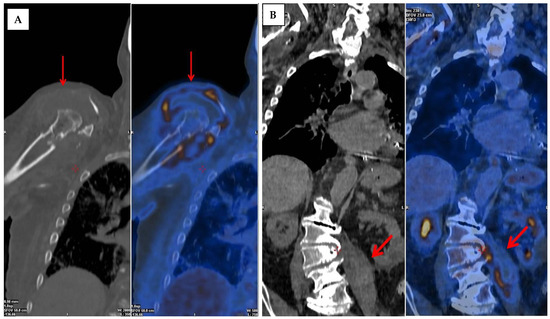

2. Fundamental Issues and Challenges Related to Conventional NM Techniques in Bone Infections

3.2. Fluorine-18-Fluorodeoxyglucose (18F-FDG) with Positron Emission Tomography (PET/CT)

3.3. Fluorine-18-Fluorodeoxyglucose (18F-FDG) PET/MRI